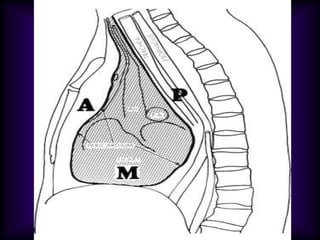

Mediastinal Cysts

The CT features of benign

mediastinal cyst are

(a) a smooth, oval or tubular mass with a well-

defined thin wall that usually enhances after

intravascular administration of contrast

material,

(b) homogeneous attenuation, usually in the

range of water attenuation (0–20 HU),

(c) no enhancement of cyst contents, and

(d) no infiltration of adjacent mediastinal

structures.